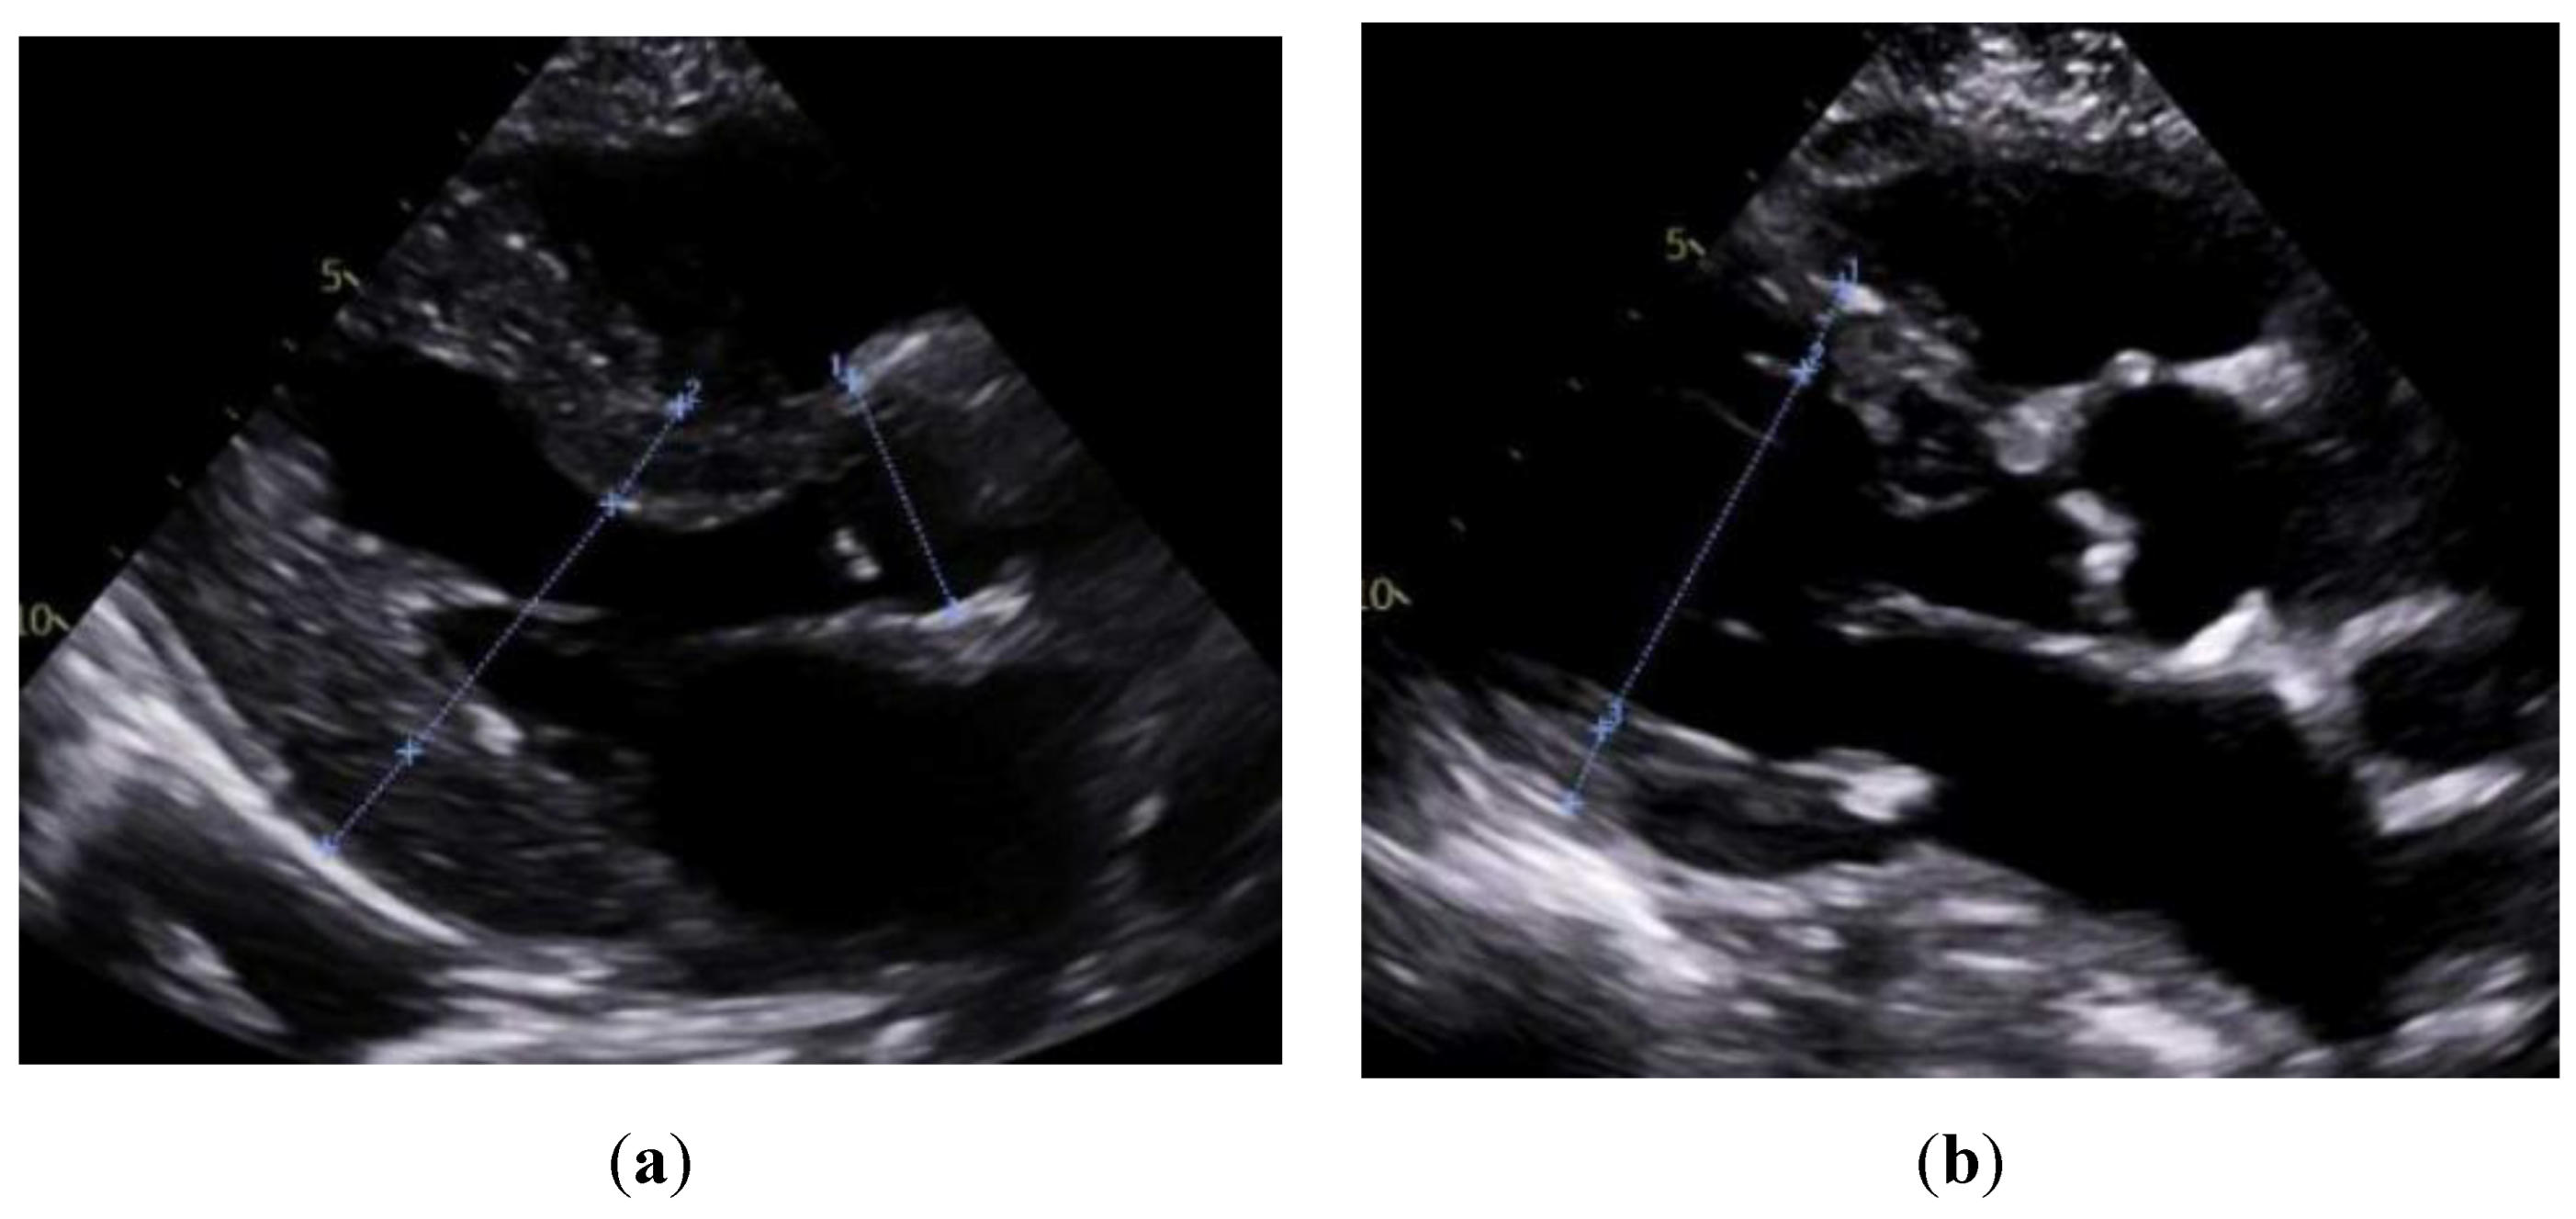

| TTE | EF | 48 ± 15 | 49 ± 14 | 0.70 |

| IVSd | 1.57 ± 0.35 | 1.10 ± 0.25 | 0.01 | |

| LVPWd | 1.45 ± 0.34 | 1.04 ± 0.18 | 0.01 | |